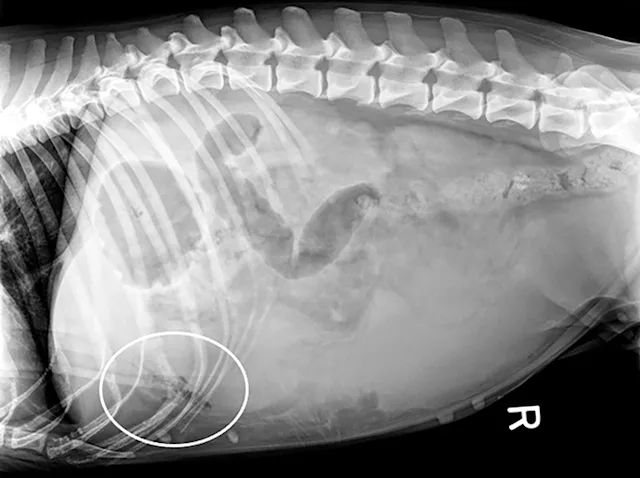

Right lateral radiographs of a clinically normal dog (A) and an 11-year-old neutered male dachshund with diabetes mellitus (B). The dog with diabetes mellitus has a pendulous abdomen and an enlarged liver (ie, hepatomegaly) with rounded margins that extend caudal to the costal arch (B; arrows). The gastric axis (solid lines; aligned with the gastric fundus dorsally to the antrum ventrally) is parallel to the ribs in the clinically normal dog but caudally displaced in the dog with hepatomegaly. Common differential diagnoses for generalized hepatomegaly are vacuolar hepatopathy due to endocrinopathies or other metabolic disease (eg, lipidosis), infectious and noninfectious inflammatory disease, neoplasia, storage disease, and venous congestion.